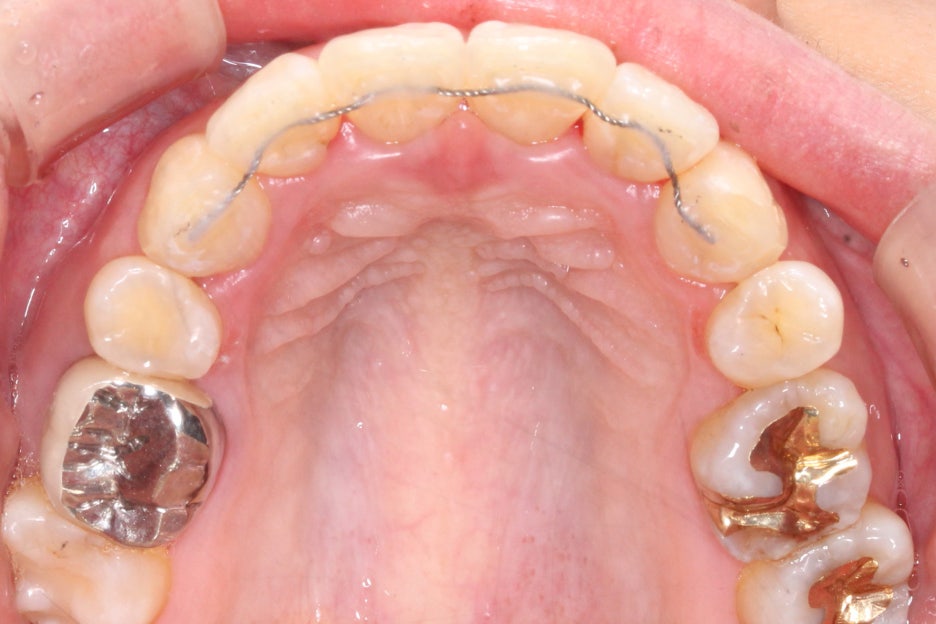

상하악의 교합면에서도

미세하게 삐뚤거리는

치열을 확인할 수 있는데요,

윗니와 아랫니의 중심이

잘 맞지 않는 상태이기 때문에

부분 교정이지만 최대한

교합을 맞추어 보도록 하겠습니다.

#11, #21 crowding 중심으로

돌출감이 심했던 윗니의

비발치 클리피씨 교정 후

정면 모습입니다.

부분교정으로 상악치열이

초기보다 확연하게

가지런해진 모습인데요,

전치부를 개방했을 때

보이는 치아의 높이도

일정하게 맞추어져서

스마일라인의 심미성이

보완된 모습입니다.